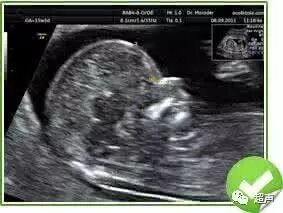

NT就是英文的nuchal translucency的缩写,翻译中文就是颈项透明层,通俗的讲就是胎儿脖子后面的一个透明带,那么检查的方法可想而知就是B超了,使用超声波查看胎儿的NT是早孕期筛查胎儿遗传物质异常的一个非常重要的技术手段,尤其是多胎妊娠。

按美国妇产科协会的指南来讲,NT检查最好是在妊娠的11到14周之间进行,过早还看不到NT,那么过晚的话异常的胎儿NT也会消失,这个窗口期是非常珍贵的。

那么NT到底为什么会反应胎儿遗传物质异常呢?因为胎儿早期淋巴液的回流会经过脖子汇入锁骨下的血管,如果遗传物质异常,可能导致回流异常,脖子下面就会积攒大量淋巴液,导致B超下面看到NT增厚,可以提示胎儿遗传物质异常,早作进一步处理。而14周以后,即使遗传物质异常的胎儿,NT也会消失,所以错过这个时期就不能行NT检查了。